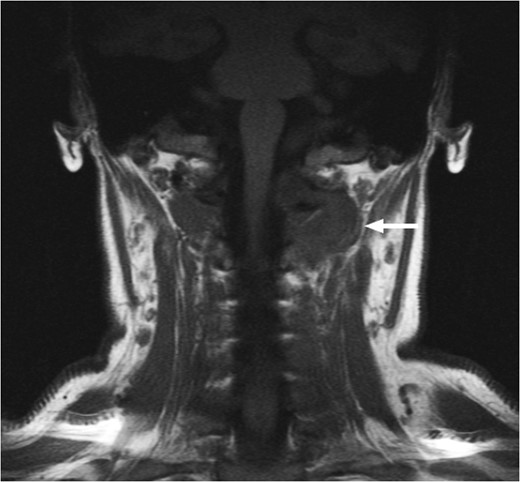

T1-weighted MRI showing the lesion in the posterosuperior aspect of the left neck arising at the level of C1, eroding through the C1 vertebra and displacing the thecal sac.